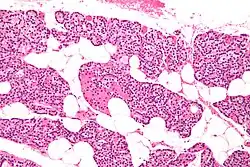

Histología

Histológicamente están rodeadas de una cápsula y contienen dos tipos de células, las células principales que son las más numerosas y producen hormona paratiroidea (PTH) y las células oxífilas, menos numerosas pero de mayor tamaño, que se distribuyen de forma irregular y no tienen vesículas secretoras a diferencia de las células principales. Existe además una cantidad variable de tejido adiposo que no tiene función endocrina directa, pero puede contribuir al soporte estructural de la glándula.[7]